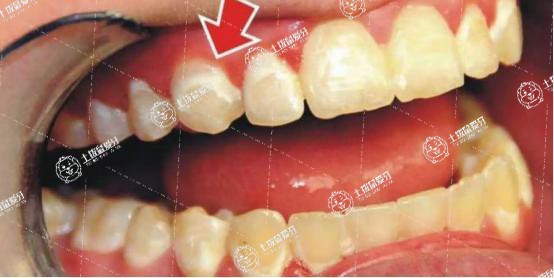

如果智齒嚴(yán)重影響下頜第二磨牙導(dǎo)致牙槽骨吸收,或者在拔牙過程中以鄰牙為支點(diǎn)暴力敲擊,則可能會(huì)出現(xiàn)第二磨牙的松動(dòng)。

剛剛拔完智齒之后,如果是相鄰的其他牙齒出現(xiàn)牙酸,那么有可能是正常現(xiàn)象,也有可能是異常的現(xiàn)象,比如說智齒是近中阻生,那么它有可能會(huì)頂?shù)角懊嫦噜彽难例X,所以造成前面相鄰牙齒遠(yuǎn)中鄰面的齲齒,就有可能是中度齲齒,有可能是深度的齲齒。